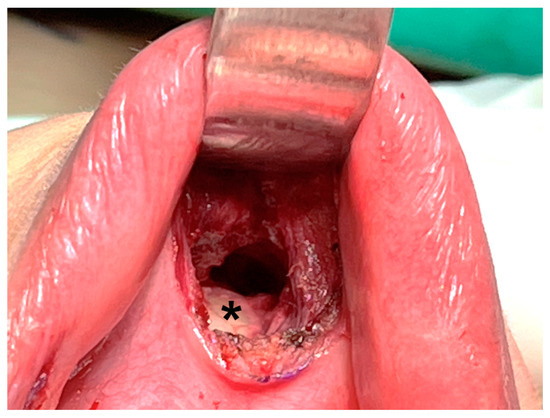

Hence, some surgeons prefer deeper dissection at the periosteum level of the mandible (Figure 4) [16,39,43]. Dissection through this layer goes underneath the mentalis muscle, and the muscle can be mostly preserved, decreasing the associated risk of muscle bleeding [43]. In addition, obtaining a thicker skin flap lowers the risk of flap perforation. Anatomic studies suggest that the periosteal approach allows easier access to the subplatysmal space [44].

Figure 4.

Dissection is performed deeper at the periosteal level (asterisk) of the mandible.